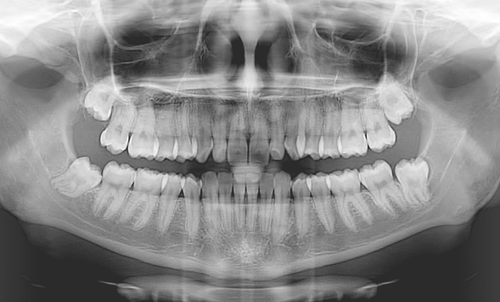

L’imaging 2D/3D per la diagnosi radiografica odontoiatrica

Le nuove tecnologie potenti e semplificate per l’imaging panoramico e la radiodiagnostica dentale

Quando e perché eseguire una tac dentale

Se l’ortopantomografia 2D non basta, oggi è possibile utilizzare la tecnologia Cone-Beam 3D